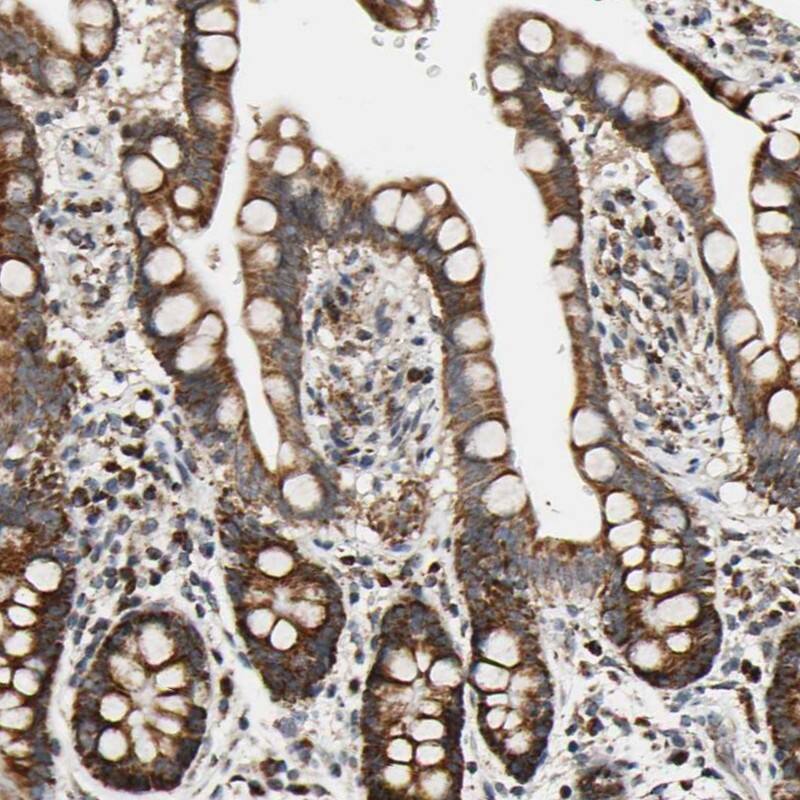

Immunocytochemistry/Immunofluorescence: KIAA0907 Antibody [NBP1-86485] - Immunofluorescent staining of human cell line U-251 MG shows localization to nucleoplasm.Immunohistochemistry-Paraffin: KHDC4 Antibody - BSA Free [NBP1-86485]

Staining of human colon shows strong cytoplasmic positivity in glandular cells.Applications for KHDC4 Antibody - BSA Free